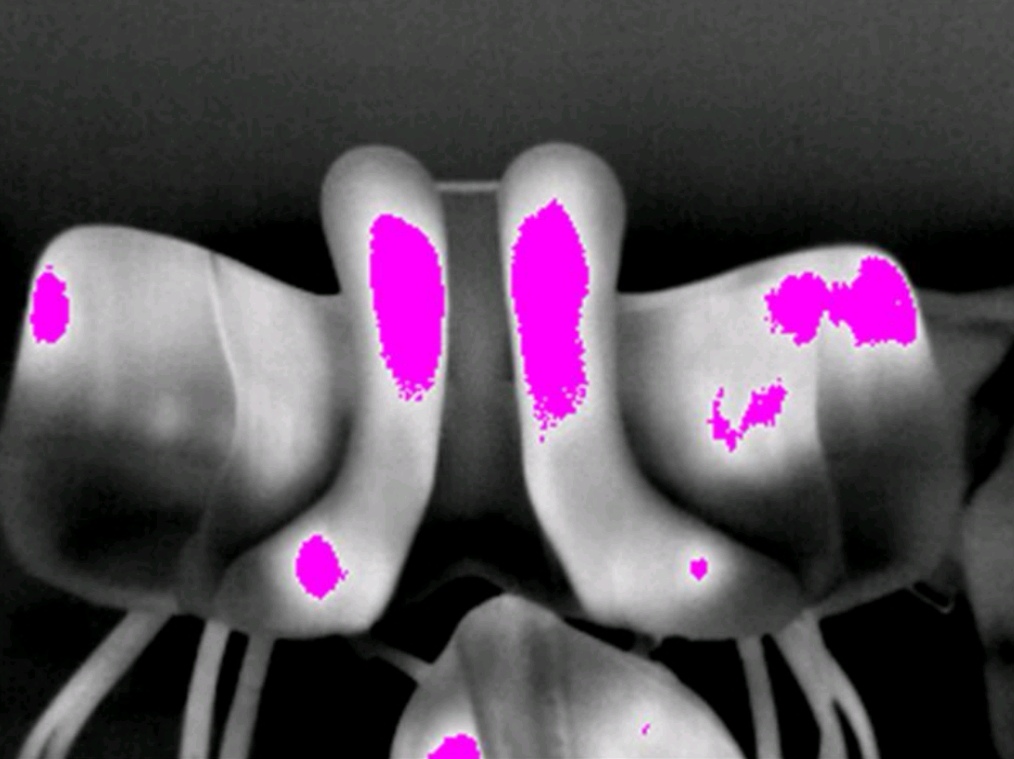

entzündete, gestresste und gereizte Bereiche

Asymmetrie im Bereich der Sattellage

Fehlerhafte Polsterung

Zu enger Wirbelkanal

Falscher Schwerpunkt

Druckspitze Steigbügelaufhängung

WAS PASSIERT NACH DEN AUFNAHMEN VOR ORT?

jedes Bild wird nachbearbeitet und bezeichnet. Es werden Markierungen wie z.B. Hotspots gesetzt. Der Kunde erhält einen Bericht mit den auffälligen Bildern